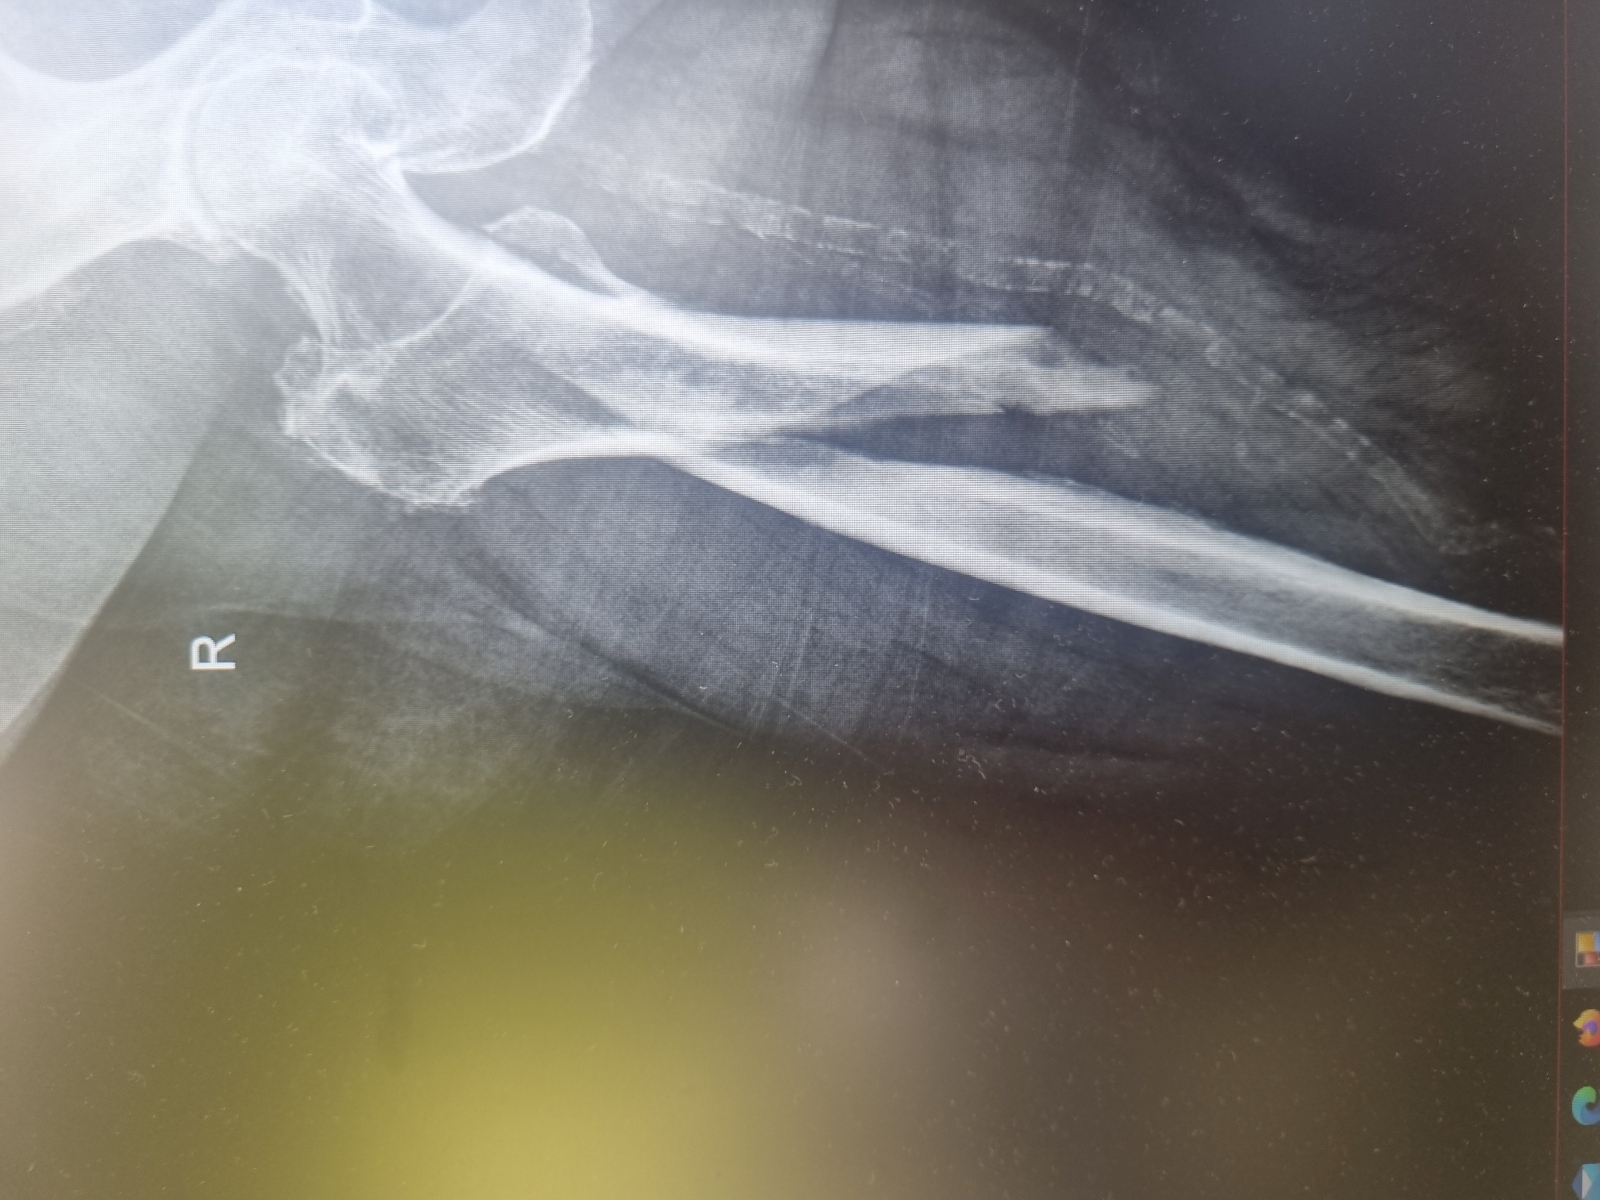

Miednica i kończyna dolna